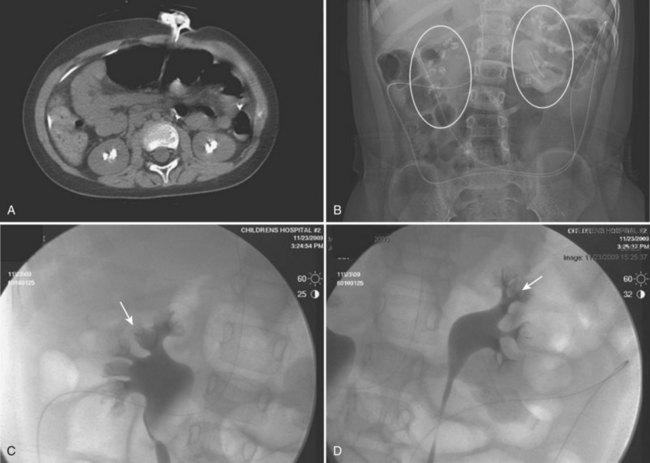

Figure 135–1 CT scan (A) and retrograde pyelogram (B) in a 10-year-old female with glucose transport deficiency demonstrating a 9-mm renal pelvic stone (arrowheads). Nephrolithiasis was secondary to profound hypocitruria and hypercalciuria. Primary ureteroscopy could not be accomplished because of a narrowed segment of proximal ureter (arrow). Following 8 weeks of ureteral accommodation with an indwelling stent, flexible ureteroscopy with laser lithotripsy and stone basketing was performed.

Figure 135–5 Altered anatomy in a 17-year-old male spina bifida patient who underwent a high thoracic myelomeningocele closure at birth (A). A computed tomography (CT) scan performed for a gross hematuria workup revealed bilateral nephrolithiasis in pelvic kidneys (B). The right retrograde pyelogram (C) demonstrated the lower pole stone (short arrow) and a torturous ureter almost taking a perpendicular course (long arrow). Placement of a ureteral access sheath (D) straightened the ureter (white arrow). This allowed easier access to address the stone (short arrow in D) with a flexible ureteroscope (E).

Figure 135–8 A 9-year-old boy with cerebral palsy and gross hematuria. CT scan demonstrated bilateral nephrolithiasis (A) thought to be staghorn calculi. Plain radiograph (B) and bilateral retrograde pyelograms (C and D) correlate to show nephrocalcinosis (white circles and white arrows, respectively) reflective of medullary sponge kidney disease. Subsequent metabolic workup revealed renal tubular acidosis (RTA) with hypercalciuria.